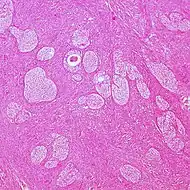

| Adult granulosa cell tumor | 1% | Almost 100% | Small, bland, cuboidal to polygonal cells in various patterns.[20] | ![]() |